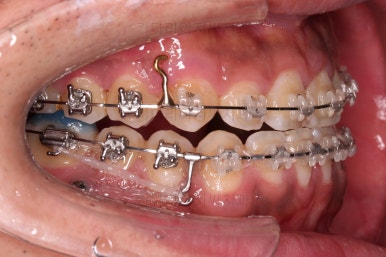

우선 치열이 가지런해졌으면 우리의 목표인 치열을 통째로 뒤로 미는 과정을 진행합니다.

잇몸뼈에 미니스크류라고 하는 아주 작은 임플란트를 식립하고요.

미니스크류를 이용해서 뒤로 당겨주게 됩니다.

어느 정도 아랫니가 뒤로 와서 위아래의 교합이 맞춰졌다 생각들면 윗니도 함께 뒤로 당겨줍니다.

그래야 뻗쳐있던 앞니의 각도도 좋아지고, 코-입술 각도(비순각)도 좋아지기 때문이죠.